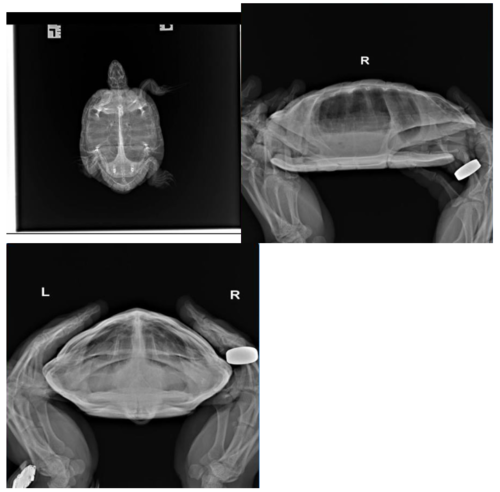

Консультанты moth Ваше имя: Мария Локация: Москва Опубликовано: 25 сентября 2022 Консультанты Опубликовано: 25 сентября 2022 @Андрей Жихарев самое простое из диагностики - сделать рентген в 3х проекциях и посмотреть нет ли яиц, газов, инородных предметов, какого-то скрытого воспаления лёгких. А дальше уже думать по результатам.

Консультанты moth Ваше имя: Мария Локация: Москва Опубликовано: 26 сентября 2022 Консультанты Опубликовано: 26 сентября 2022 @Андрей Жихарев только сразу предупреждаю - ничего ей колоть не нужно, если вдруг врач захочет. Ни антибиотики, ни витамины. Обычный ветеринар понятия не имеет как лечить рептилий и в большинстве случаев делает только хуже. Ваша задача сделать рентген, желательно в трёх проекциях. Но если по деньгам туго, то в одной лежа на животе

Консультанты moth Ваше имя: Мария Локация: Москва Опубликовано: 26 сентября 2022 Консультанты Опубликовано: 26 сентября 2022 @Андрей Жихарев вот настройки для рентгена: Настройки обычно: 67кВ на 2мА/сек Также допустимо 50кВ на 6-8мА/сек